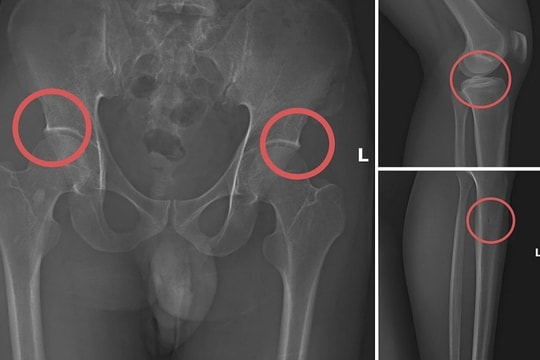

Cách cán bộ y tế dùng búa đinh đục gãy xương chân để trục lợi bảo hiểm

Tạ Minh Châu, nguyên cán bộ y tế, đã cho người mua bảo hiểm nhân thọ giá trị cao, rồi tiêm thuốc mê, dùng búa đinh đục gãy xương chậu, đùi của họ để cùng trục lợi tiền.